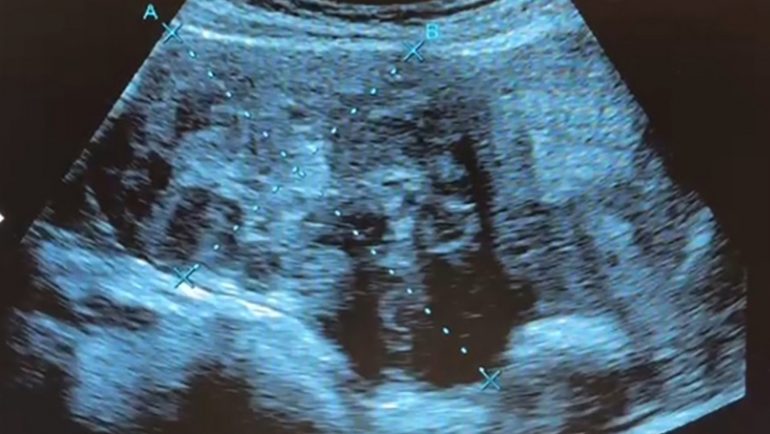

35歲女性患者的超音波影像,十字區域範圍為9公分大子宮肌瘤體積。(記者陳金龍攝) 記者陳金龍∕台中報導 一位35歲上班族女子即將結婚,擔心多年來檢查發現的多顆子宮肌瘤會造成不孕,婚前就醫檢查,發現體內子宮肌瘤又多又大,是屬於年輕型的子宮肌瘤患者,因體質及年紀輕,血中雌激素刺激讓子宮肌瘤快速長大,患者接受達文西機械手臂手術,由肚臍開刀取出9顆肌瘤,從1到9公分不等共9顆,最大肌瘤大如拳頭般,但手術沒有明顯傷口,把傷口隱藏在肚臍裡。 澄清醫院中港院區婦產科醫師謝昌興說,患者子宮肌瘤從1到9公分不等共9顆,最大顆有拳頭大。(記者陳金龍攝) 澄清醫院中港院區婦產科醫師謝昌興指出,子宮肌瘤是雌激素敏感的腫瘤,婦女一生中發生機率約35%以上,為女性最常見的良性婦科腫瘤,一般來說,女性停經後,隨著血中雌激素濃度下降,肌瘤會逐漸縮小。 但子宮肌瘤的成長有其機制,如果年紀輕輕就長子宮肌瘤,因體內雌激素較旺盛,雌激素會刺激肌瘤快速長大,這名婦人的子宮肌瘤又多又大,與年紀較輕相關,女性在35歲至45歲,是子宮肌瘤最常好發的年齡。 婦人多年來有頻尿、便秘的困擾,尤其在排卵期會嚴重腹脹,幾年前就醫婦產科診所檢查發現有多顆肌瘤,最近因為快要結婚了,怕影響受孕,經介紹到謝昌興門診就診。 謝昌興表示,患者的子宮肌瘤不是長在子宮腔內,而是長在子宮璧並往外生長,子宮猶如圓凸形,這類子宮肌瘤在手術摘除後,子宮的功能恢復正常,能自然受孕及生產;如果肌瘤往子宮腔面生長,可能有不孕問題。 患者因工作和婚期考量,接受達文西手臂手術,能較快復原。手術在肚臍劃開一個3公分傷口,手臂進入腹腔,切除肌瘤,縫合傷口,再將過大肌瘤切割成小塊,從肚臍小傷口取出,接著縫合肚臍小傷口,術後看不出有傷口,住院3天出院就能上班工作。